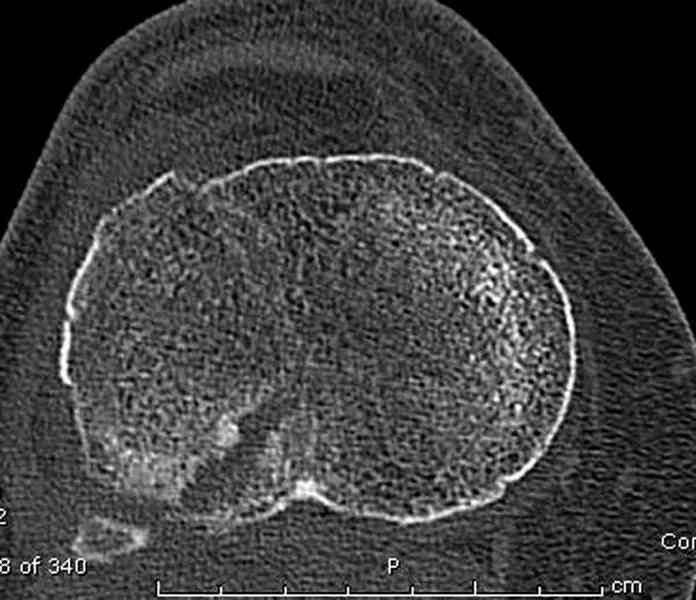

Для внутрисуставных переломов необходимо идеальное сопоставление, а такая задача без КТ срезов усложнится. Только КТ надо делать после дистракции сустава, иначе нельзя получить объективную информацию.

Основная задача в лечении околосуставных переломов является создание солидного базиса в субхондральной зоне. Пластина подпорка (Butress) или субхондральные перкутанные шурупы в виде плота (Raft) для ранних движении.